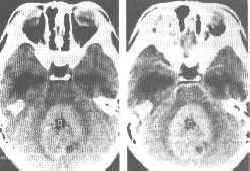

髓母细胞瘤(CT)

小脑蚓部髓母细胞瘤。CT平扫(左图)示小脑蚓部圆形高、低混合密度病灶,边界尚清,周围伴轻度水肿。第四脑室闭塞。增强后(右图)示实质部分明显强化,低密度区物强化。